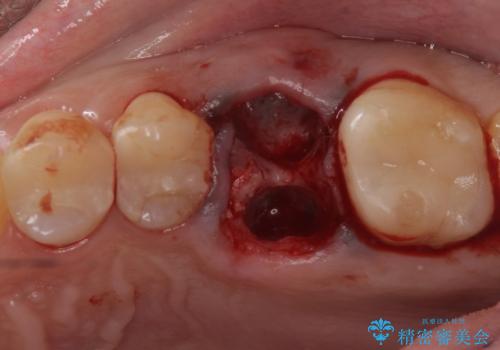

- 検査の結果、長くもたせることが困難な歯が確認された患者様です。

抜歯を行い、周囲の骨を増やしつつインプラントを埋入することとなりました。

良い位置に良い方向でインプラントを埋入することができました。